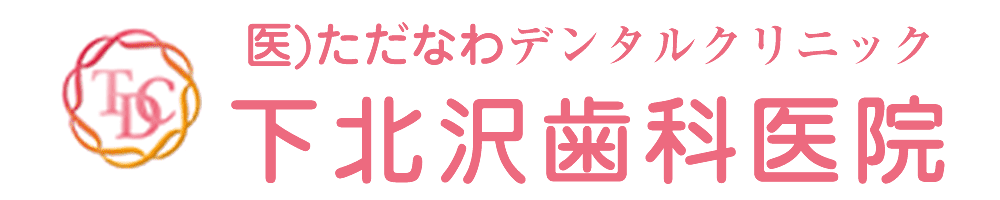

まず残っている歯の根を抜き、中の感染が起きてしまっている所をキレイに掻爬し、人工の根を入れて骨を作るところまでを1回の処置で行いました。

今回は頬側の骨が吸収されて無くなってしまっていたので、そこの回復もする事ができるような骨造成を行いました。これらの処置を1回で行う事により、2回に分けてやるよりも骨の減りを最小限に留め、治療期間を短くする事ができます。